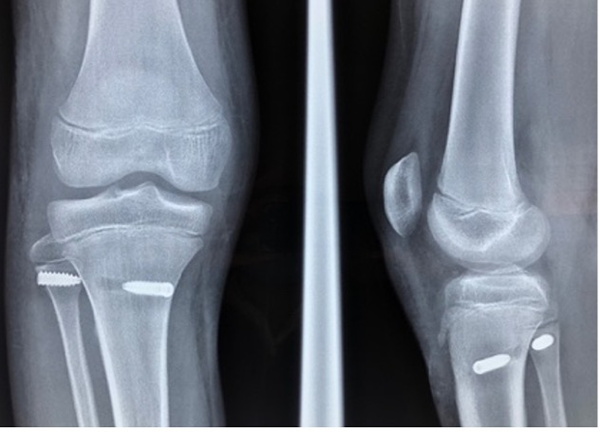

Se colocó al paciente en decúbito dorsal, en mesa convencional. Se colocó torniquete y se realizó un abordaje posterolateral de rodilla. Se disecó por planos cuidadosamente, identificando el nervio peroneo común que se protegió durante la intervención. Se evidenció la lesión intrasustancia del LTPP. Una vez identificada la fisis bajo visión radiológica, se confeccionó túnel en peroné de unos 6 mm de diámetro, 3 cm distal a la misma. Se efectuó un abordaje interno en tibia proximal sobre la pata de ganso y se extrajo con stripper una vez liberado el semitendinoso. Se realizó túnel de 6 mm de diámetro en tibia por debajo y posterior al músculo poplíteo y anterior, medial y distal al tubérculo de Gerdy; todos los túneles se realizaron bajo control radioscópico intraoperatorio. Luego de pasado el injerto, se fijó con tornillo de interferencia en tibia y peroné (fig. 3).

Se realizó control radiográfico en el postoperatorio inmediato el que presentó buena posición de los túneles y la articulación tibioperonea proximal reducida (fig. 4).

Figura 3: Fotos intraoperatorias. A) Abordaje posterolateral nervio peroneo común reparado. B) Colocación de pin para confección de túnel peroneo. C) Pasada de injerto a través del túnel tibial. D) Fijación con tonillo de interferencia túnel peroneo.

Figura 4: Postoperatorio inmediato, buena posición de los túneles. Articulación tibioperonea proximal reducida.